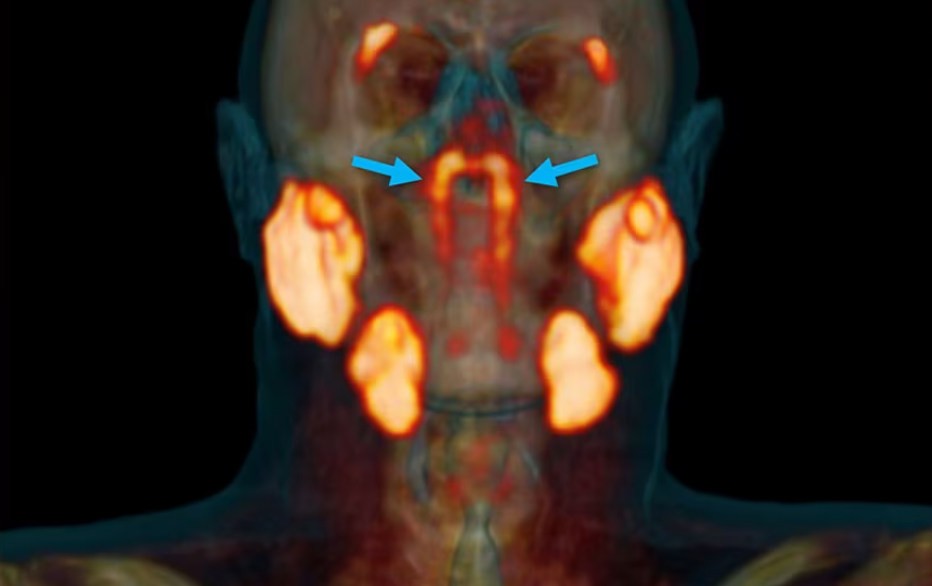

El equipo utilizó una técnica de imagen conocida como PET/TC con PSMA, una herramienta altamente sensible usada comúnmente en oncología. A diferencia de la resonancia magnética o la ecografía, este método permitió observar con gran detalle estructuras internas del cuello y la cabeza. Gracias a esta tecnología, el descubrimiento del ¿nuevo órgano en el cuerpo humano? fue posible.

Los investigadores nombraron a estas nuevas glándulas como glándulas tubáricas. Aunque todavía se debate si deberían ser clasificadas como un nuevo órgano, el estudio sugiere que podrían tener una función específica en la producción de saliva. La frase “glándulas salivales menores” fue utilizada por algunos especialistas para tratar de ubicarlas dentro de la anatomía ya existente.